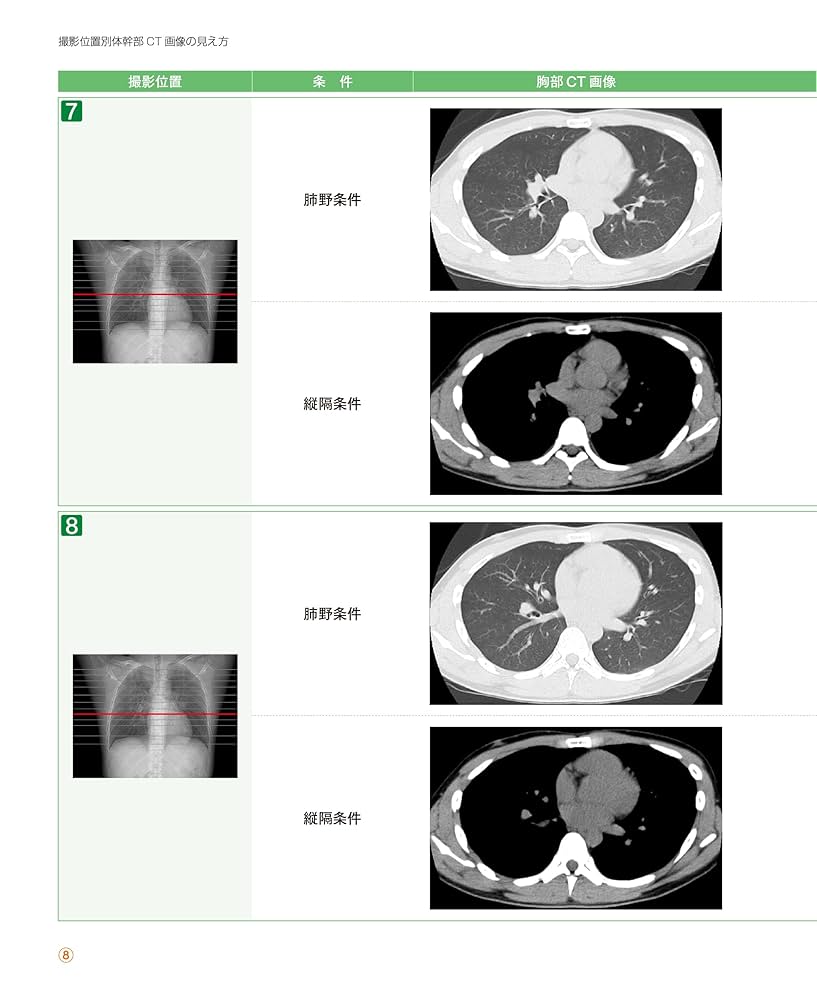

HOT ! 看護 看護アセスメント力を高める!画像検査まるわかり (NsCan) | 酒井

看護 看護アセスメント力を高める!画像検査まるわかり (NsCan) | 酒井の詳細情報

看護アセスメント力を高める!画像検査まるわかり (NsCan) | 酒井。ケアセフティ CSS-81 | ミドリ安全のベルデクセル・メディカル。☆<すみっコぐらし>高反発インソールスニーカー: ナース。看護関連の本です。☆<すみっコぐらし>高反発インソールスニーカー: ナース。看護学生、看護師さんにおすすめです!自宅保管のため、神経質な方はご遠慮ください(。。>д<)ご希望の方は専用つくりますのでコメントお願いいたします!まとめ購入されるかた優先させていただきます!一冊当たりを半額で考えての値段設定にしております!

• 看護アセスメント力を高める!画像検査まるわかり (NsCan) | 酒井